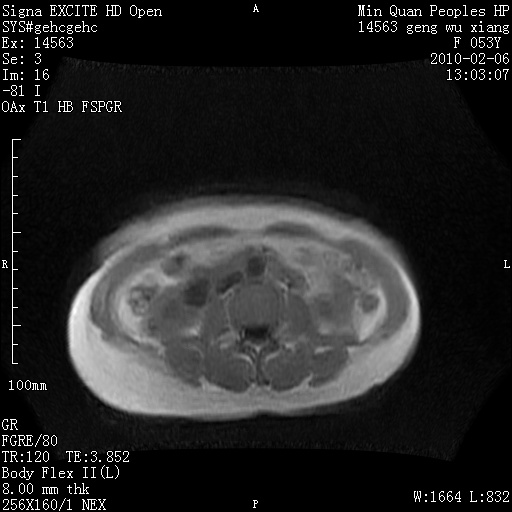

标题: MRI2762:胆道梗阻原因?

f,53y,全身黄染多日。

高位胆道梗阻 胆管癌可能性大

支持 高位胆道梗阻 胆管癌可能性大。